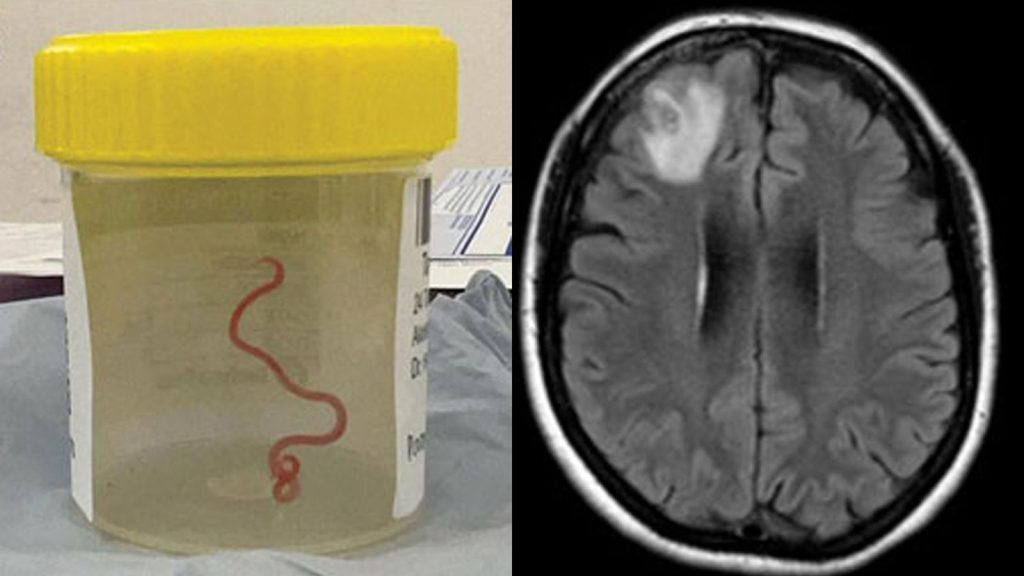

Uma ressonância magnética de seu cérebro revelou que um helminto móvel – uma lombriga parasita – vivia na lesão do lobo frontal direito de seu cérebro.

A intervenção cirúrgica tornou-se a única opção e os médicos removeram com sucesso a lombriga, que media 8 cm (80 mm) de comprimento e 1 mm de diâmetro.

Identificado como uma larva de terceiro estágio da espécie de nematóide Ophidascaris robertsi, o caso não tem precedentes na história da medicina e foi documentado na revista Emerging Infectious Diseases.

Durante o procedimento cirúrgico, uma “estrutura semelhante a um fio” incomum foi descoberta dentro da lesão e, para espanto dos médicos, ela começou a se contorcer.

O exame do verme indicou sua afiliação a uma família de parasitas tipicamente exclusiva de cobras. Isto marcou o primeiro caso documentado de tal parasita infectando um ser humano.